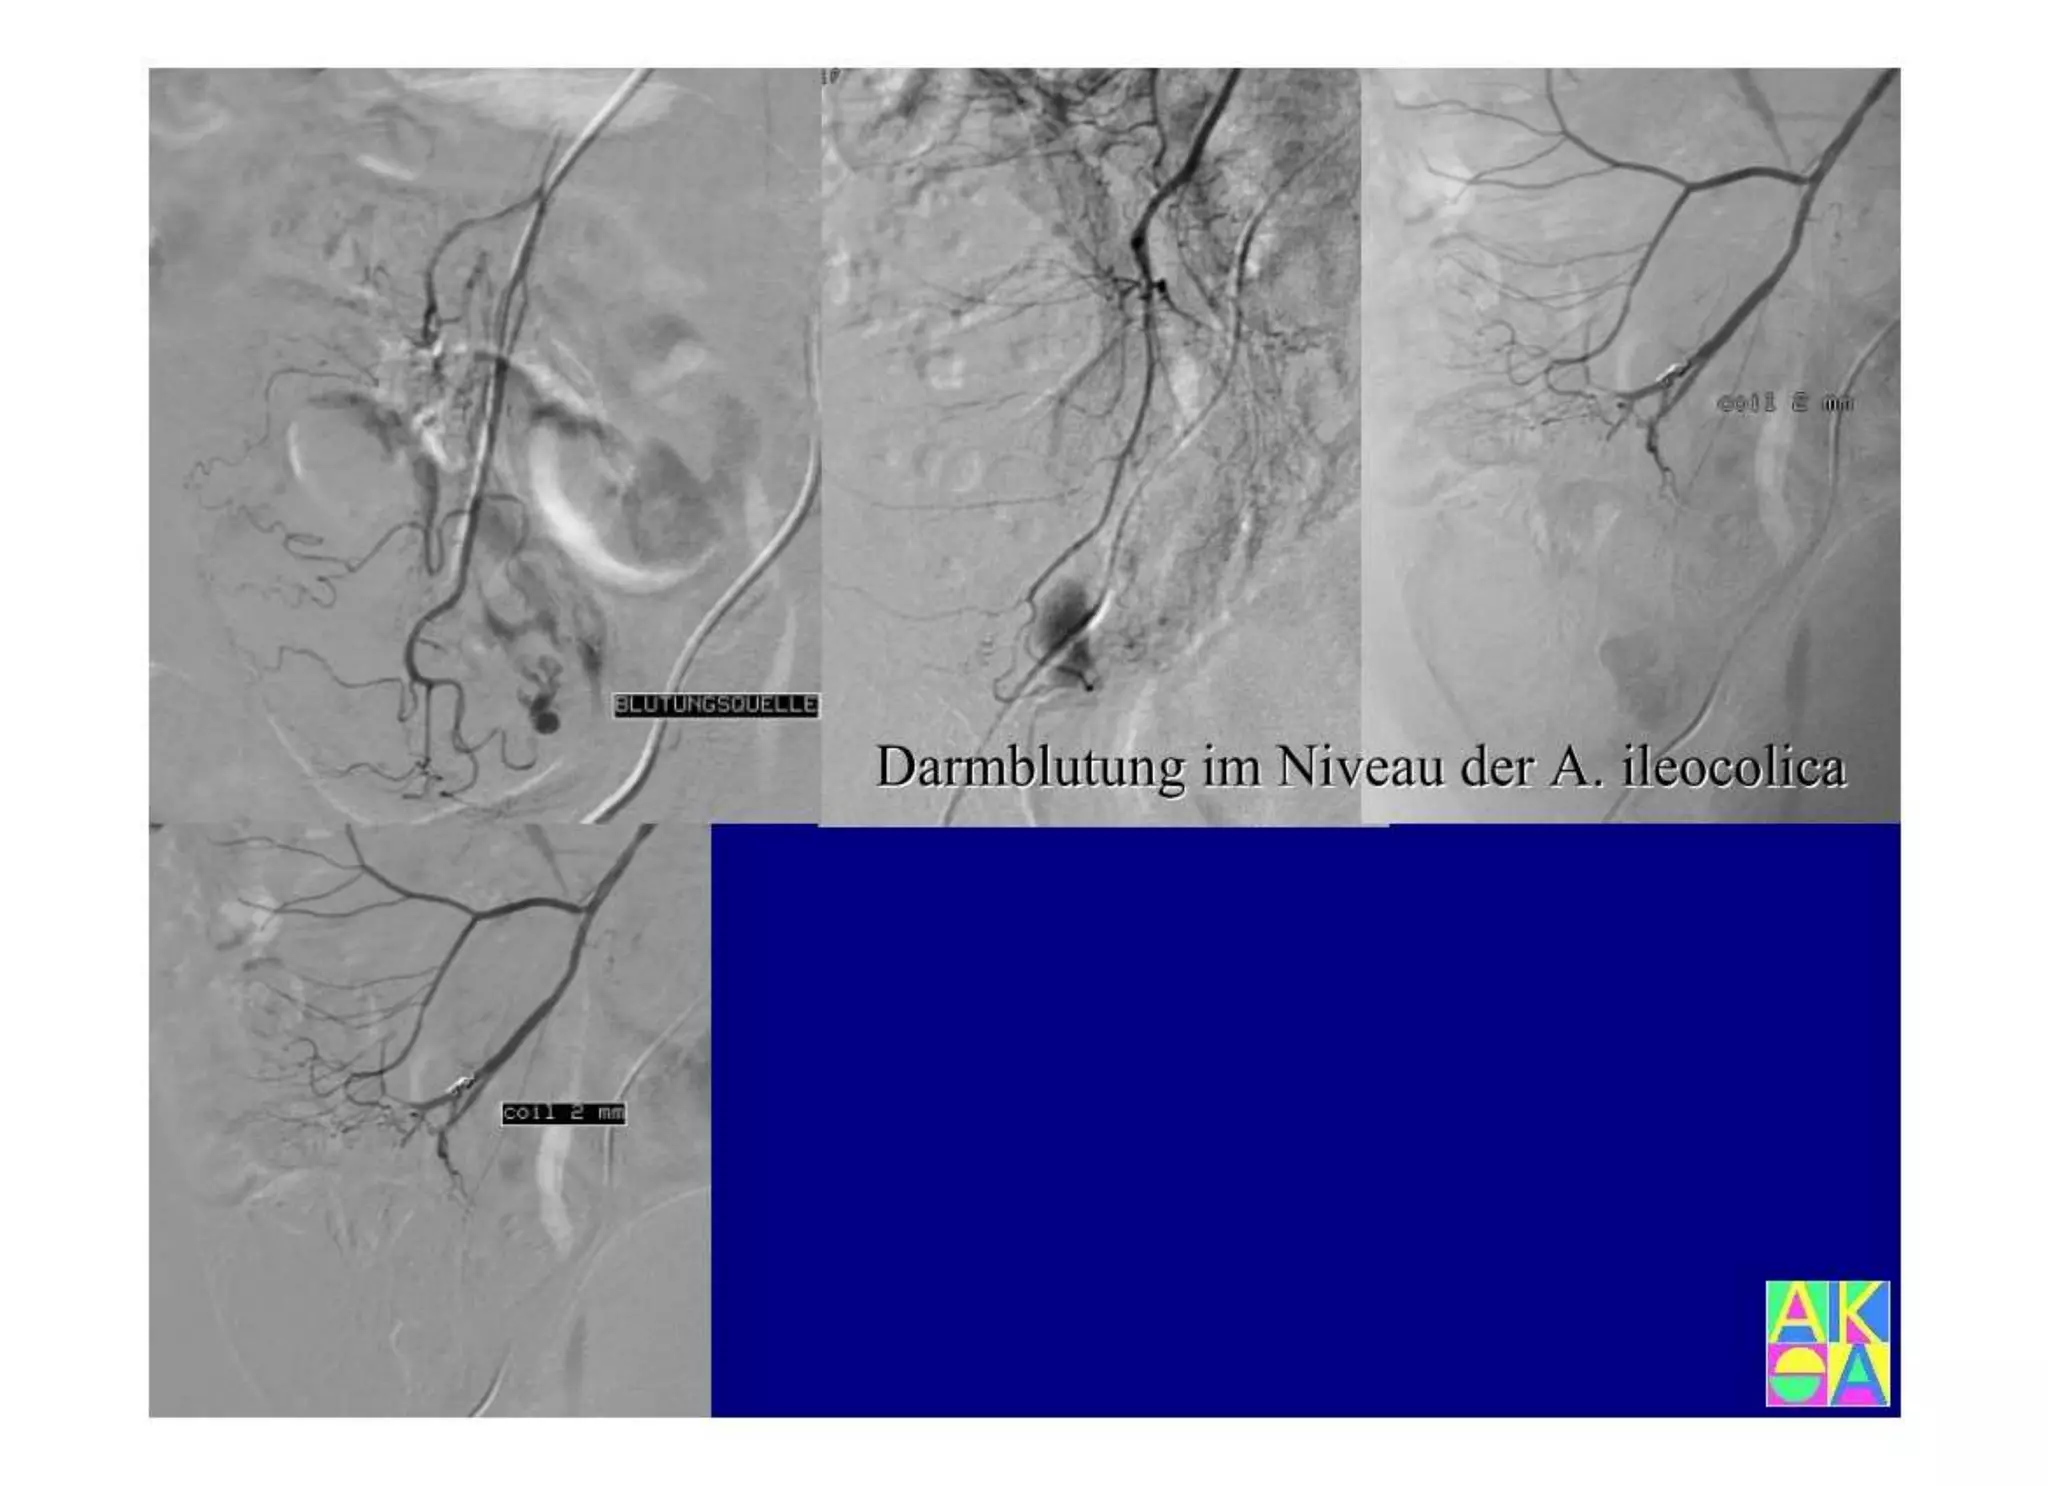

Chronische Enteropathie und Ileus, Dünndarm und Dickdarmdiagnostik, Mechanischer und paralytischer Ileus, Eingeklemmte Darmabschnitte, aufgereihter Bridenileus, und dazu Dickdarmileus, eingeklemmte Hernien, Weitergabeskript